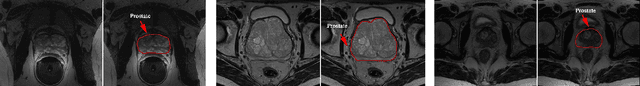

Abstract:Precise determination of target is an essential procedure in prostate interventions, such as the prostate biopsy, lesion detection and targeted therapy. However, the prostate delineation may be tough in some cases due to tissue ambiguity or lack of partial anatomical boundary. To address this problem, we proposed a weakly supervised registration-based framework for the precise prostate segmentation, by combining convolutional neural network (CNN) with statistical shape model (SSM). To obtain the prostate region, an inception-based neural network (SSM-Net) was firstly exploited to predict the model transform, shape control parameters and a fine-tuning vector, for the generation of prostate boundary. According to the inferred boundary, a normalized distance map was calculated. Then, a residual U-net (ResU-Net) was employed to predict a probability label map from the input images. Finally, the average of the distance map and the probability map was regarded as the prostate segmentation. After that, two public dataset PROMISE12 and NCI- ISBI 2013 were utilized for the model computation and for the network training and testing. The validation results demonstrate that the segmentation framework using a SSM with 9500 nodes achieved the best performance, with a dice of 0.904 and an average surface distance of 1.88 mm. In addition, we verified the impact of model elasticity augmentation and fine-tuning item on the network segmentation capability. As a result, both factors have improved the delineation accuracy, with dice increased by 10% and 7% respectively. In conclusion, via the combination of two weakly supervised neural networks, our segmentation method might be an effective and robust approach for prostate segmentation.